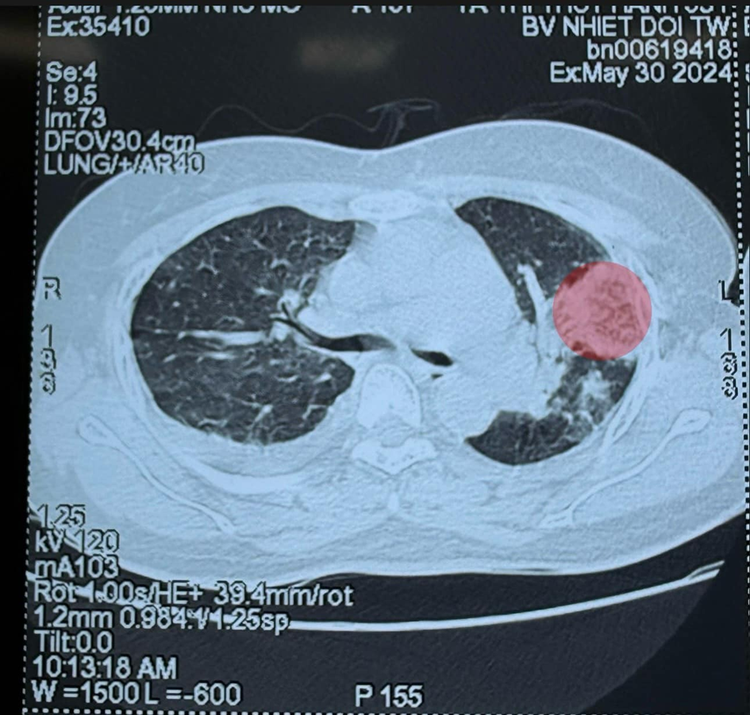

Phổi đông đặc sau 7 ngày SXH

Bệnh nhân chuyển đến Bệnh viện Bệnh Nhiệt đới Trung ương vào ngày thứ 7 của SXH, có tình trạng bội nhiễm. Chụp cắt lớp phổi cho thấy các đám đông đặc rải rác, có nhiều ổ áp xe ở trong phổi... Kết quả cấy máu ra vi khuẩn tụ cầu vàng kháng Methicillin (tụ cầu kháng thuốc).

Bệnh nhân sốt xuất huyết đồng nhiễm vi khuẩn, phổi đông đặc